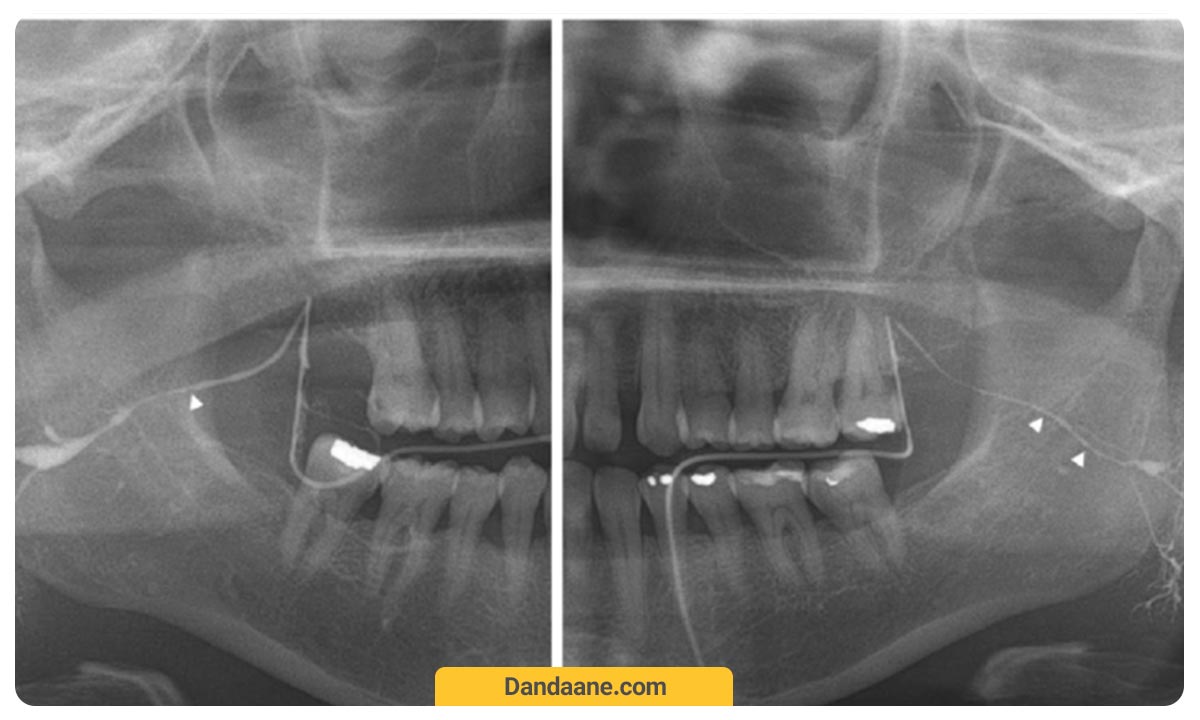

عکس بایت وینگ دندان (Bitewing)

عکسبرداری بایت وینگ تاج یا روکش دندان را به خوبی به دندانپزشک نشان می هد. در این روش دندانپزشک از هر طرف صورت و یا هر دو طرف عکس می گیرد. در هر عکس دندان بایت وینگ دندان های مولر (دندان های عقب) و دندان های پرمولر (آسیاب کوچک) در بالا و پائین و در واقع جزئیات دندان های بالا و پائین یک سمت دندان را نشان می دهد.

همچنین از عکسبرداری بایت وینگ برای تعیین میزان مناسب بودن یا نبودن روکش های دندانی و یا ترمیم های دیگری مانند بریج دندان استفاده می شود. به جز این، می توان وضعیت پر کردکی های دندانی را می توان با بایت وینگ به صورت دقیق ارزیابی کرد.

هزینه عکس بایت وینگ معمولا از قیمت و هزینه عکس دندان opg کمتر و برابر با 70 تا 100 هزارتومان است.